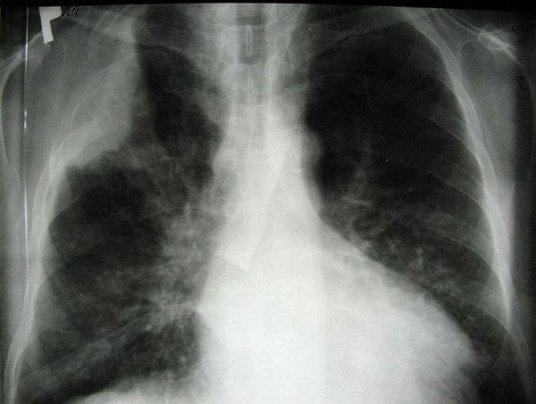

As announced by the Japanese Ministry of Health, Labor and Social Affairs (MHLW) on Tuesday, lung cancer was first recognized as a result of labor input during the disaster at the Fukushima Daiichi nuclear power plant.

The man in his mid-50s was employed at various nuclear power plants since June 1980. After the start of the Fukushima crisis in March 2011, he was commissioned with radiation measurements, but also dealt with the planning and the first measurement in decontamination work.

As the MHLW announced, the former power plant worker has since died. It is the first case in which lung cancer is recognized as a “catastrophic death”.

So far, only three cases of leukemia and one case of thyroid cancer have been recognized by former nuclear workers as a causal consequence of their work on the Fukushima Daiichi nuclear power plant. Prefecture media reported this late recognition of the lung cancer case.